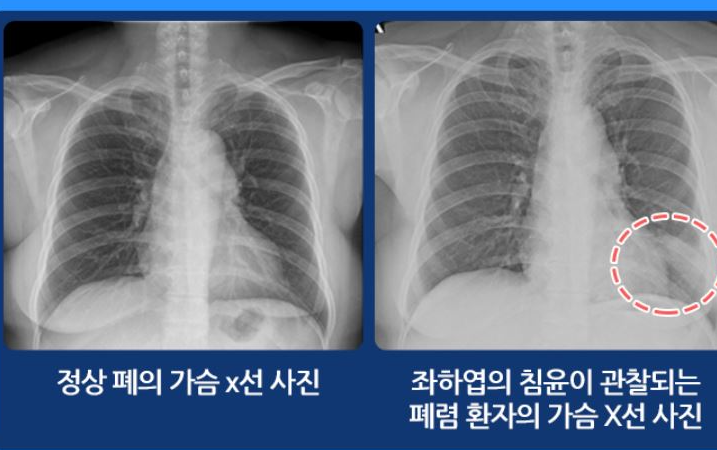

폐렴은 세균, 바이러스가 침입해 세기관지 이하 폐조직에 염증을 발생시키는 감염성 질환입니다. 증상은 통상 기침, 열, 가래등의 증상이 나타나며, 흉부의 X-RAY 검사를 통해 확인할 수 있습니다.

폐렴은 발열 및 기침, 가래 등의 호흡기 증상을 통해서 의심할 수 있습니다. 또한 흉부 X-RAY 촬영을 통해 진단합니다. 하지만 개인에 따라 증상이 다르게 나타나는 경우도 흔합니다. 이럴 때엔 균 배양이 되면 정확하게 진단이 되지만, 균 배양은 폐렴의 50% 정도에서만 이루어집니다. 또한 객담 검사, 혈액 검사, 혈청 검사, 흉막액 배양 검사 등이 시행되기도 합니다.